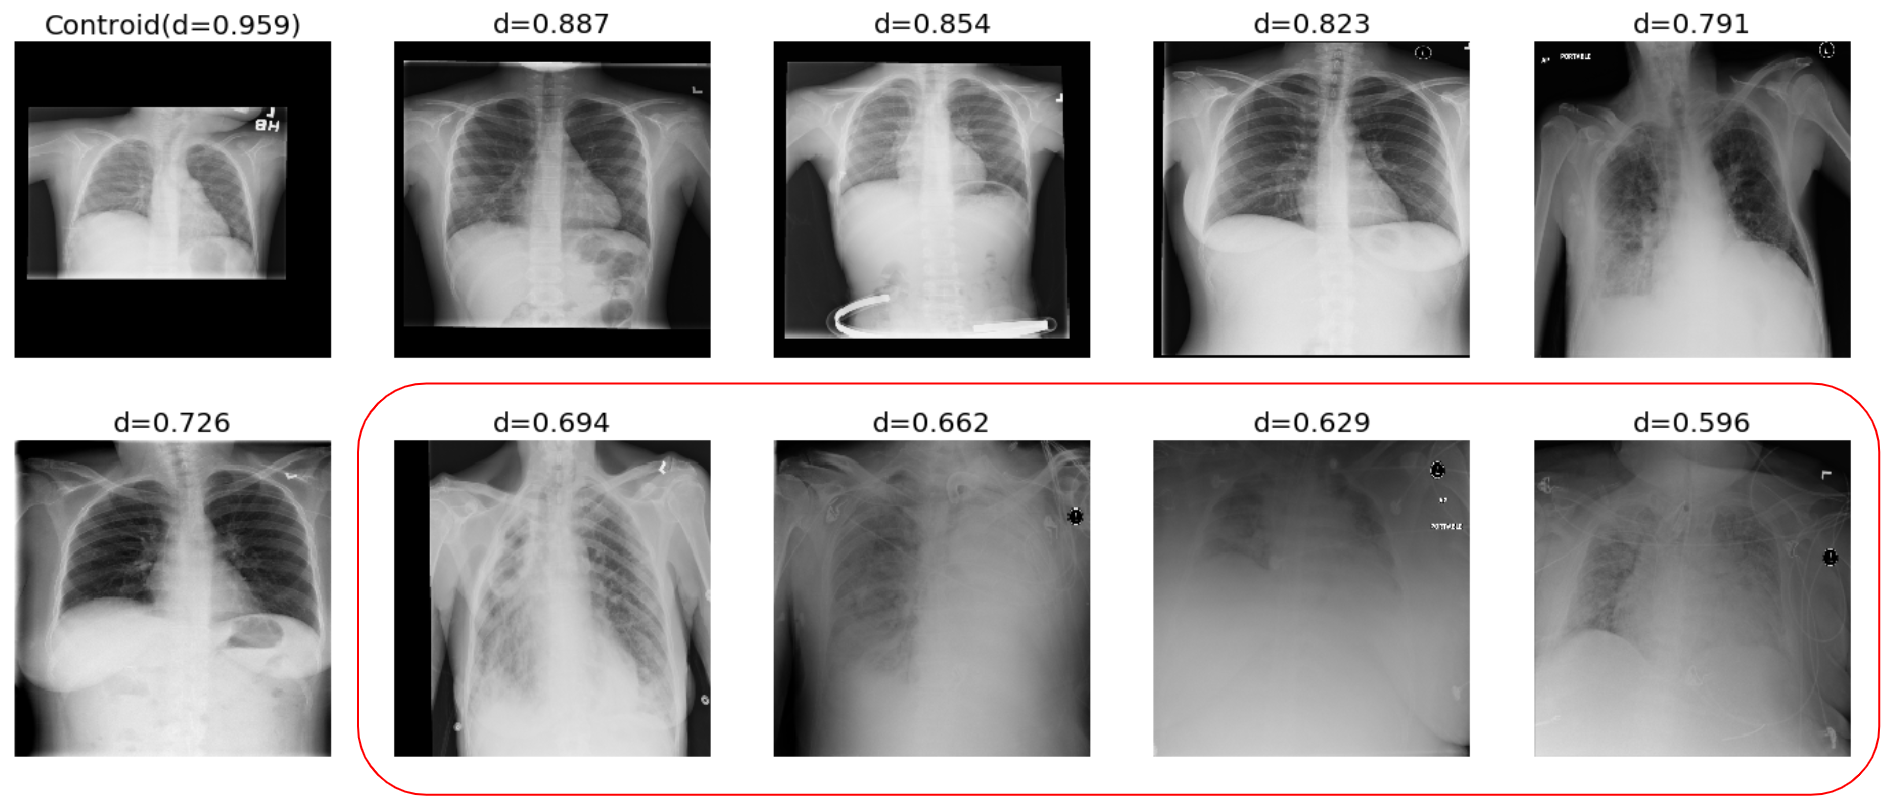

In Fig. 3 we depict six selected images and four discarded images from the class Infiltration. The first image in the upper panel is the image closest to centroid and as expected its similarity value is very high. The discarded images are selected using a threshold θ=0.7𝜃0.7\theta=0.7. Fig. 3 reveals that the discarded images are indeed poor quality images.

Figure 3: Infiltration CXRs, images in red block are ignored. d represents cosine similarity with centroid